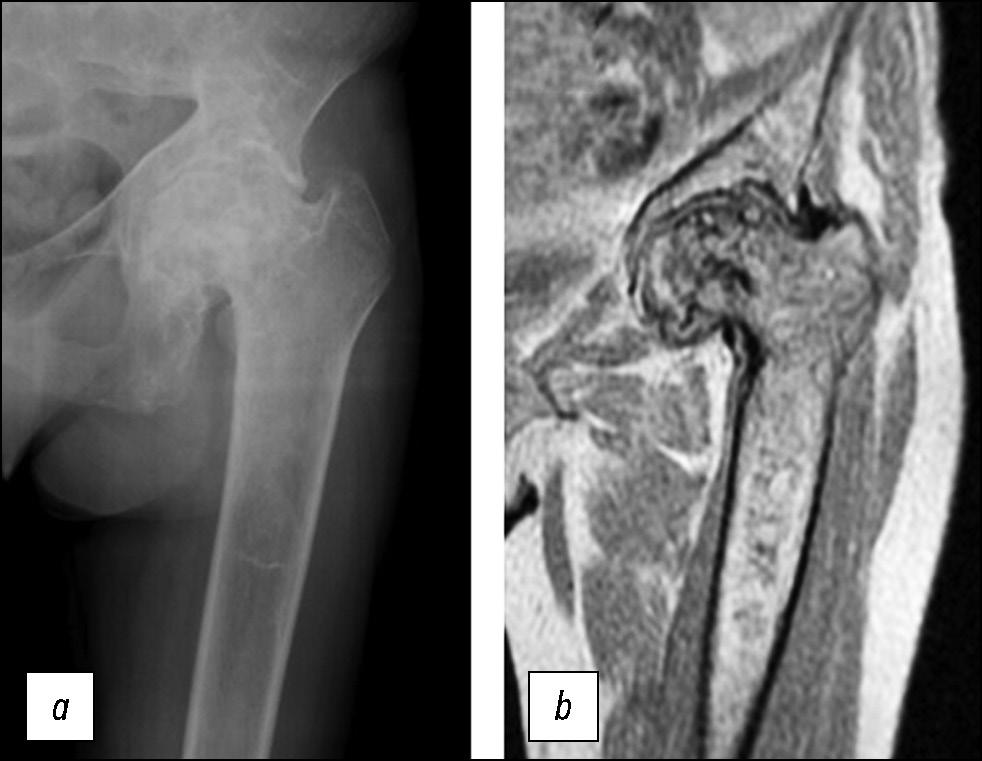

АНГБК нередко сочетался с другими костными проявлениями заболевания. Это, в первую очередь, нарушение костного ремоделирования в виде цилиндрического расширения (или вздутия) проксимального отдела диафиза бедренной кости с вторичной остеопенией и остеопорозом той же локализации (рис. 4, 5). При БГ расширение/ вздутие костномозговой полости проксимального отдела диафиза бедра не распространялось на шейку и головку, где, напротив, нередко наблюдали склерозирование губчатой кости.

Рис. 4. Рентгенограмма тазобедренного сустава в прямой проекции (a) и фрагмент МРТ Т1-ВИ (b) проксимального отдела бедренной кости. Кортикомедуллярный остеонекроз головки бедренной кости, тип 4 по классификации АRCO. Расширение полости костномозгового канала в проксимальном диафизе бедренной кости с негомогенным разрежением костной ткани на рентгенограмме, а также участками постинфарктного медуллярного остеонекроза на МРТ.

Fig. 4. X-ray of the hip in direct projection (a) and an MRI T1-WI (b) of the proximal femur. Corticomedullary osteonecrosis of the femoral head type 4 to ARCO classification. Expansion of the bone marrow canal cavity in the proximal diaphysis of the femur with inhomogeneous bone thinning on the X-ray, as well as areas of postinfarction medullary osteonecrosis on MRI.